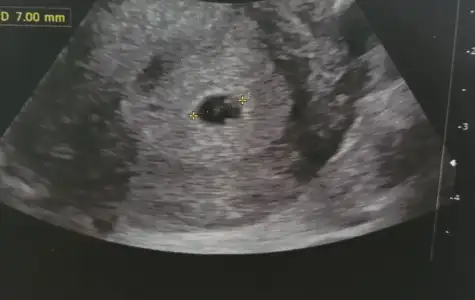

Karından usg lerde ayna etkisi yaratabiliyor. Sağı solda solu sağda gösterebiliyor. En doğrusu vajinal usgler. Vajinale göre solda bu bebiş kızmelegim can canımm bu bebiş vajınalde gecen haftaya gore diğer tarafta gozukuyo bu sefer kıza mı dondu acaba